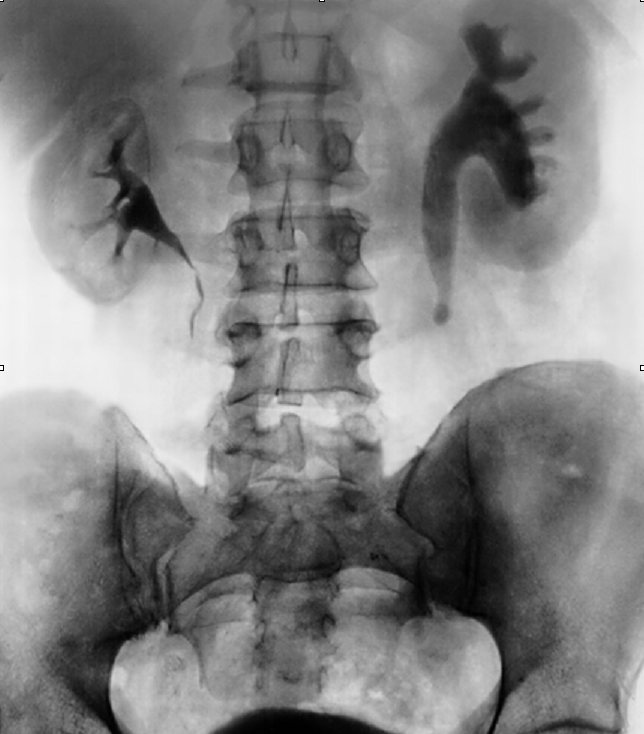

УЗИ почек является безболезненным, недорогим и достаточно информативным методом наблюдения за динамикой мочекаменной болезни и процессом растворения камней

Поскольку камни в почках могут быть рентгеноконтрастные (видимые на рентгенограмме, например, оксалаты и фосфаты) и такие, которые на рентгене не определяются (ураты), то для контроля выведения камней более применимо ультразвуковое исследование. УЗИ почек используют для диагностики камней и контроля за их выведением, поскольку эта методика позволяет обнаружить конкременты в почках разнообразной формы и размеров и даже песок. Наблюдение в динамике позволяет выявить изменение камней в размерах и визуализировать их локализацию на определённый момент времени.

Рентгеновские снимки не позволяют выявить уратные камни, поэтому для их диагностики используются ультразвуковое исследование и лабораторные анализы крови и мочи. Врач может назначить и другие методы обследования, такие как магнитно-резонансная томография (МРТ), компьютерная томография (КТ) или контрастная рентгеноскопия, если это необходимо.

Пожалуй, главная диагностическая особенность камней из мочевой кислоты — их не видно на рентгене. Обычные конкременты из кальция являются неорганической известью, и поэтому их так же хорошо видно, как кости. А здесь этот самый доступный недорогой метод скринингового исследования неэффективен. Если вспомнить, что 20% всех мочевых камней, и 80% всех камней у мужчин зрелого возраста, составляют именно ураты, то у пациентов из этой группы можно сразу считать обзорную рентгенографию брюшной полости неэффективной при подозрении на мочекаменную болезнь.

Но здесь на помощь приходит рентгеновская компьютерная томография, (РКТ или КТ), которая почти во всех случаях позволяет рассмотреть уратные конкременты. Наиболее эффективным, быстрым, и совершенно безопасным методом визуализирующей диагностики, является УЗИ почек, мочевыводящих путей и мочевого пузыря.

В том случае, если предполагается нахождение камня внутри мочеточника, то он может быть очень мелким, и на УЗИ его видно недостаточно хорошо, или незаметно вообще. Поэтому для локализации такого камня выполняют пиелографию. Чаще всего экскреторную, но можно и ретроградную. Хорошо будет виден ток контраста сверху вниз (в случае экскреторной) или снизу вверх (в случае ретроградной) пиелографии.

При этом с одной стороны, уже идет гидронефроз, с раздуванием чашечек и лоханки (целых 5 чашечек). С другой стороны, в мочеточник контраст все же попал, но, в конце концов, остановился. Скорее всего, там «каменный песок», множественные препятствия.